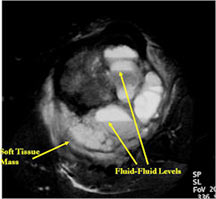

- The cystic spaces filled with hemorrhagic material leads to the presence of fluid-fluid levels on MRIs (so called ABC-like changes or telangiectatic change)

- ABC- like changes can sometimes lead to a misdiagnosis on X-rays and the tumor may be misinterpreted as being a benign ABC.

MRI/CT:

- Fluid-fluid levels secondary to cystic cavities filled with blood products. The sediment from blood products settle to the gravity dependent area of the cavity and the fluid component floats to top thus forming a fluid-fluid level.

- MRI and CT are also useful for demonstrating the local extent of the tumor and any soft tissue mass